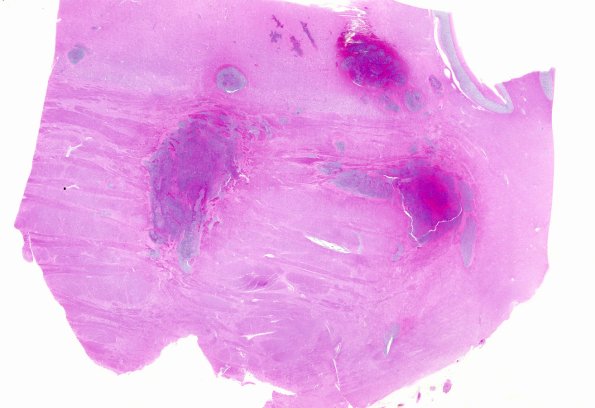

Washington University Experience | NEOPLASMS (HEMATOLYMPHOID) | Granulocytic Sarcoma | 2B1 Leukemia (Case 2) N1 WM

The hemorrhages within the pons show major participation of the cellular collections of blasts. No other leukemic nodules were found in the cerebral hemispheres. (H&E)